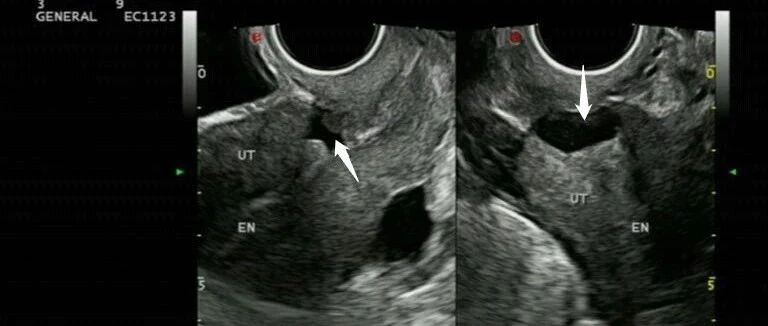

剖宫产子宫切口憩室 1 例 丁香园超声时间 · 公众号 · 医学 · 1 年前 · |